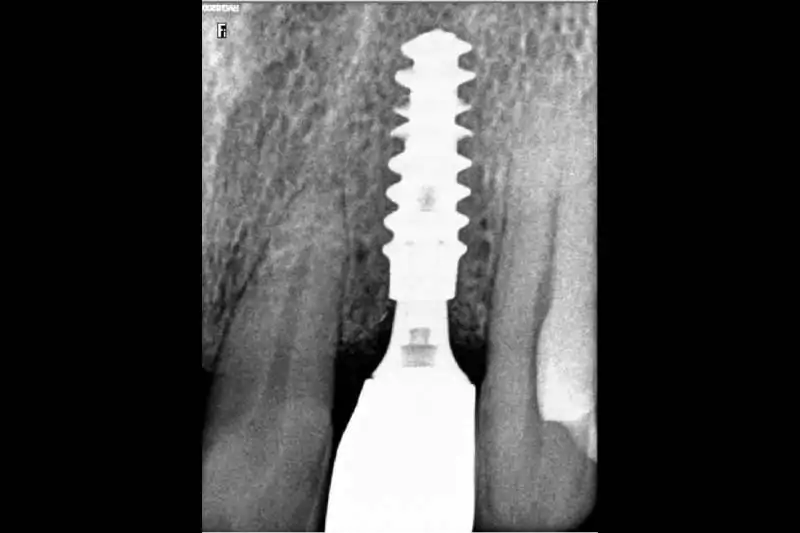

After a thorough clinical examination of your jaw bone, the Best dentist in Pune at Smilex confirms the available jaw bone by CBCT scan or X-rays. The doctors then administer a very small cut in the gums under local anesthesia. A painless drill sequence leads to the final drill position, after which the dental implants in Pune are placed in the bone. Gums are then placed back in their original position. A single implant procedure takes up to 45 mins to be done.

Usually, the permanent crowns are fitted 3 to 4 months after the implants are put in. However, in some cases (immediate implants) teeth can also be fixed at the same as the implants.

After your implants have been placed, the bone in your jaw needs to grow onto them and integrate with them. This usually takes 2-4 months. In situations where the implant is stable enough, a false tooth is immediately attached to the implant. A temporary denture is given in situations where the patient has gone through an implant procedure for more than one tooth. If you have full dentures, you can keep wearing these while your implants are healing.